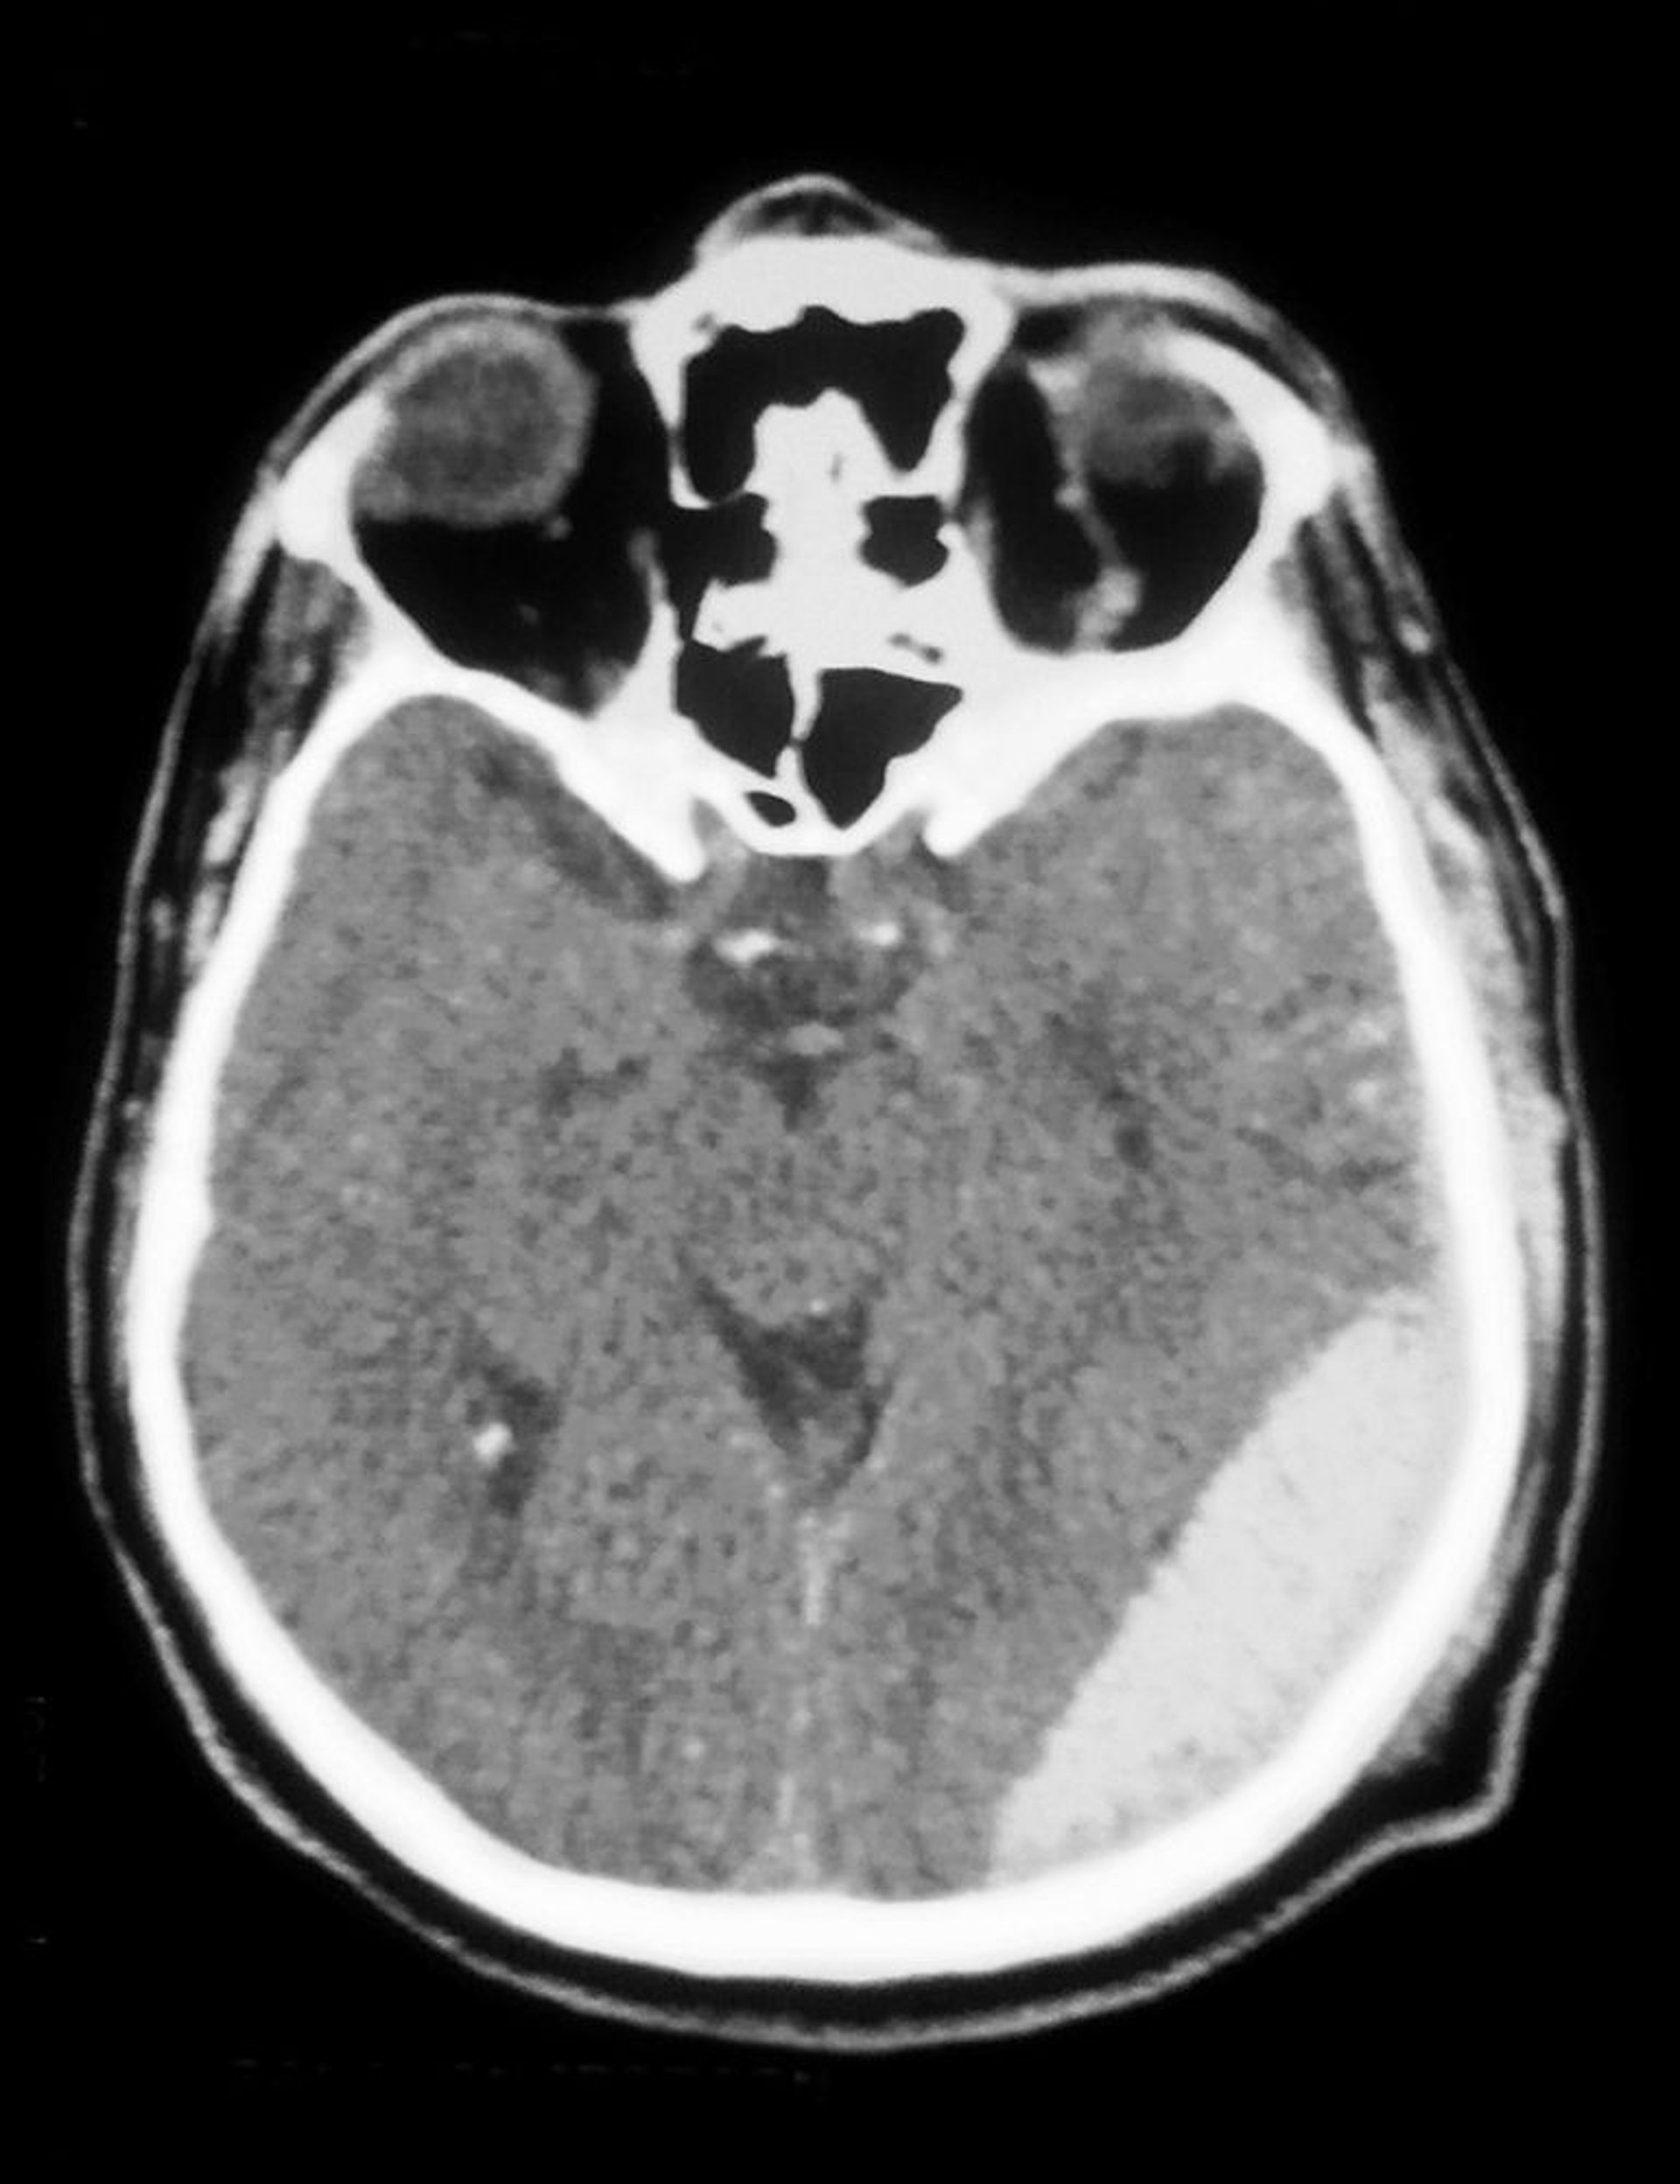

La TDM montre un hématome épidural (opacité en bas à droite).

Cavallini James/BSIP/SCIENCE PHOTO LIBRARY